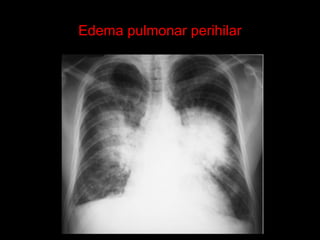

Edema pulmonar perihilar ( asas de

morcego ).

Edema pulmonar perihilar